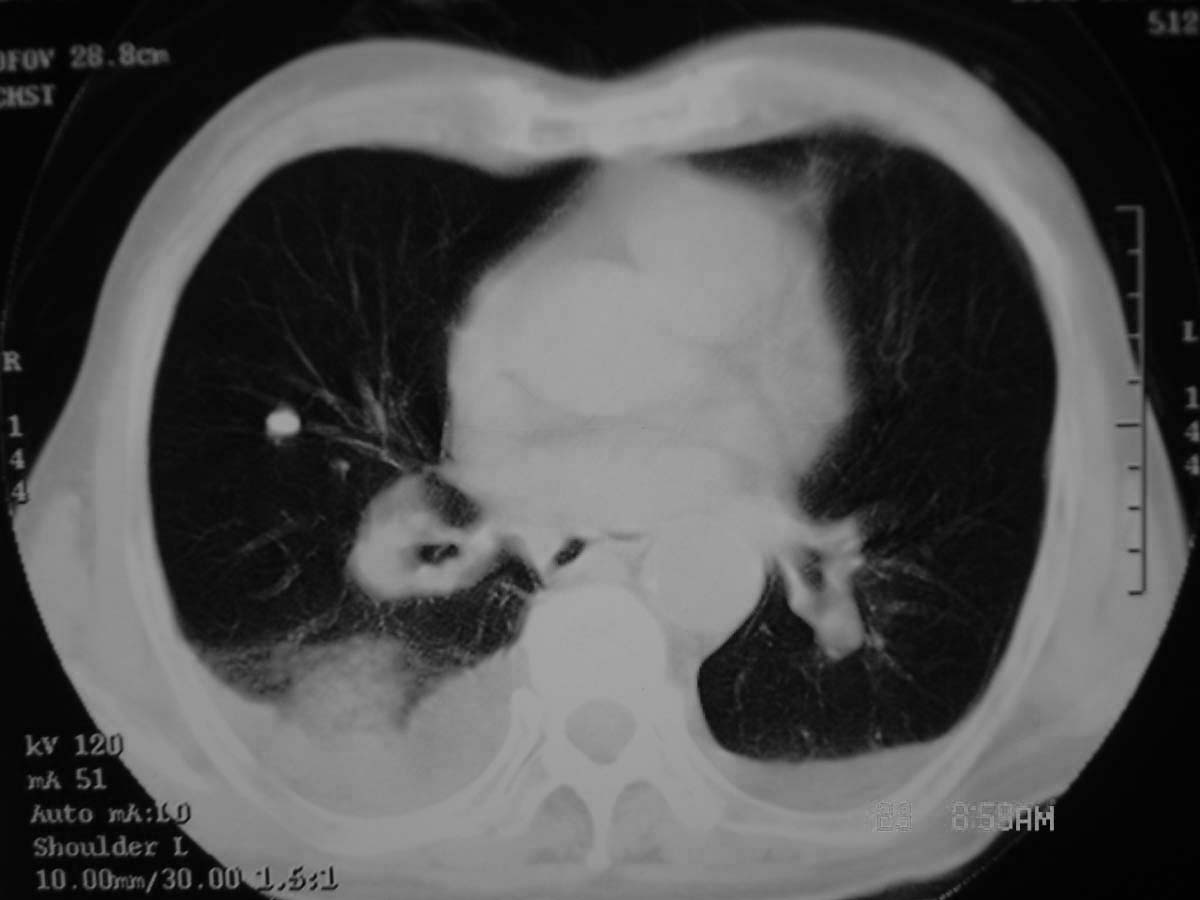

以下是引用守望可可西里在2006-11-23 14:33:00的发言:[br][br] 糖尿病病人很容易继发结核,病人又有双侧胸膜增厚、粘连、胸腔积液以及双上肺的斑片状、条索状影结核病灶影,以一元论考虑,右下肺病变首先考虑干酪性肺炎,可以正规抗炎治疗后复查,排除一般的肺炎。